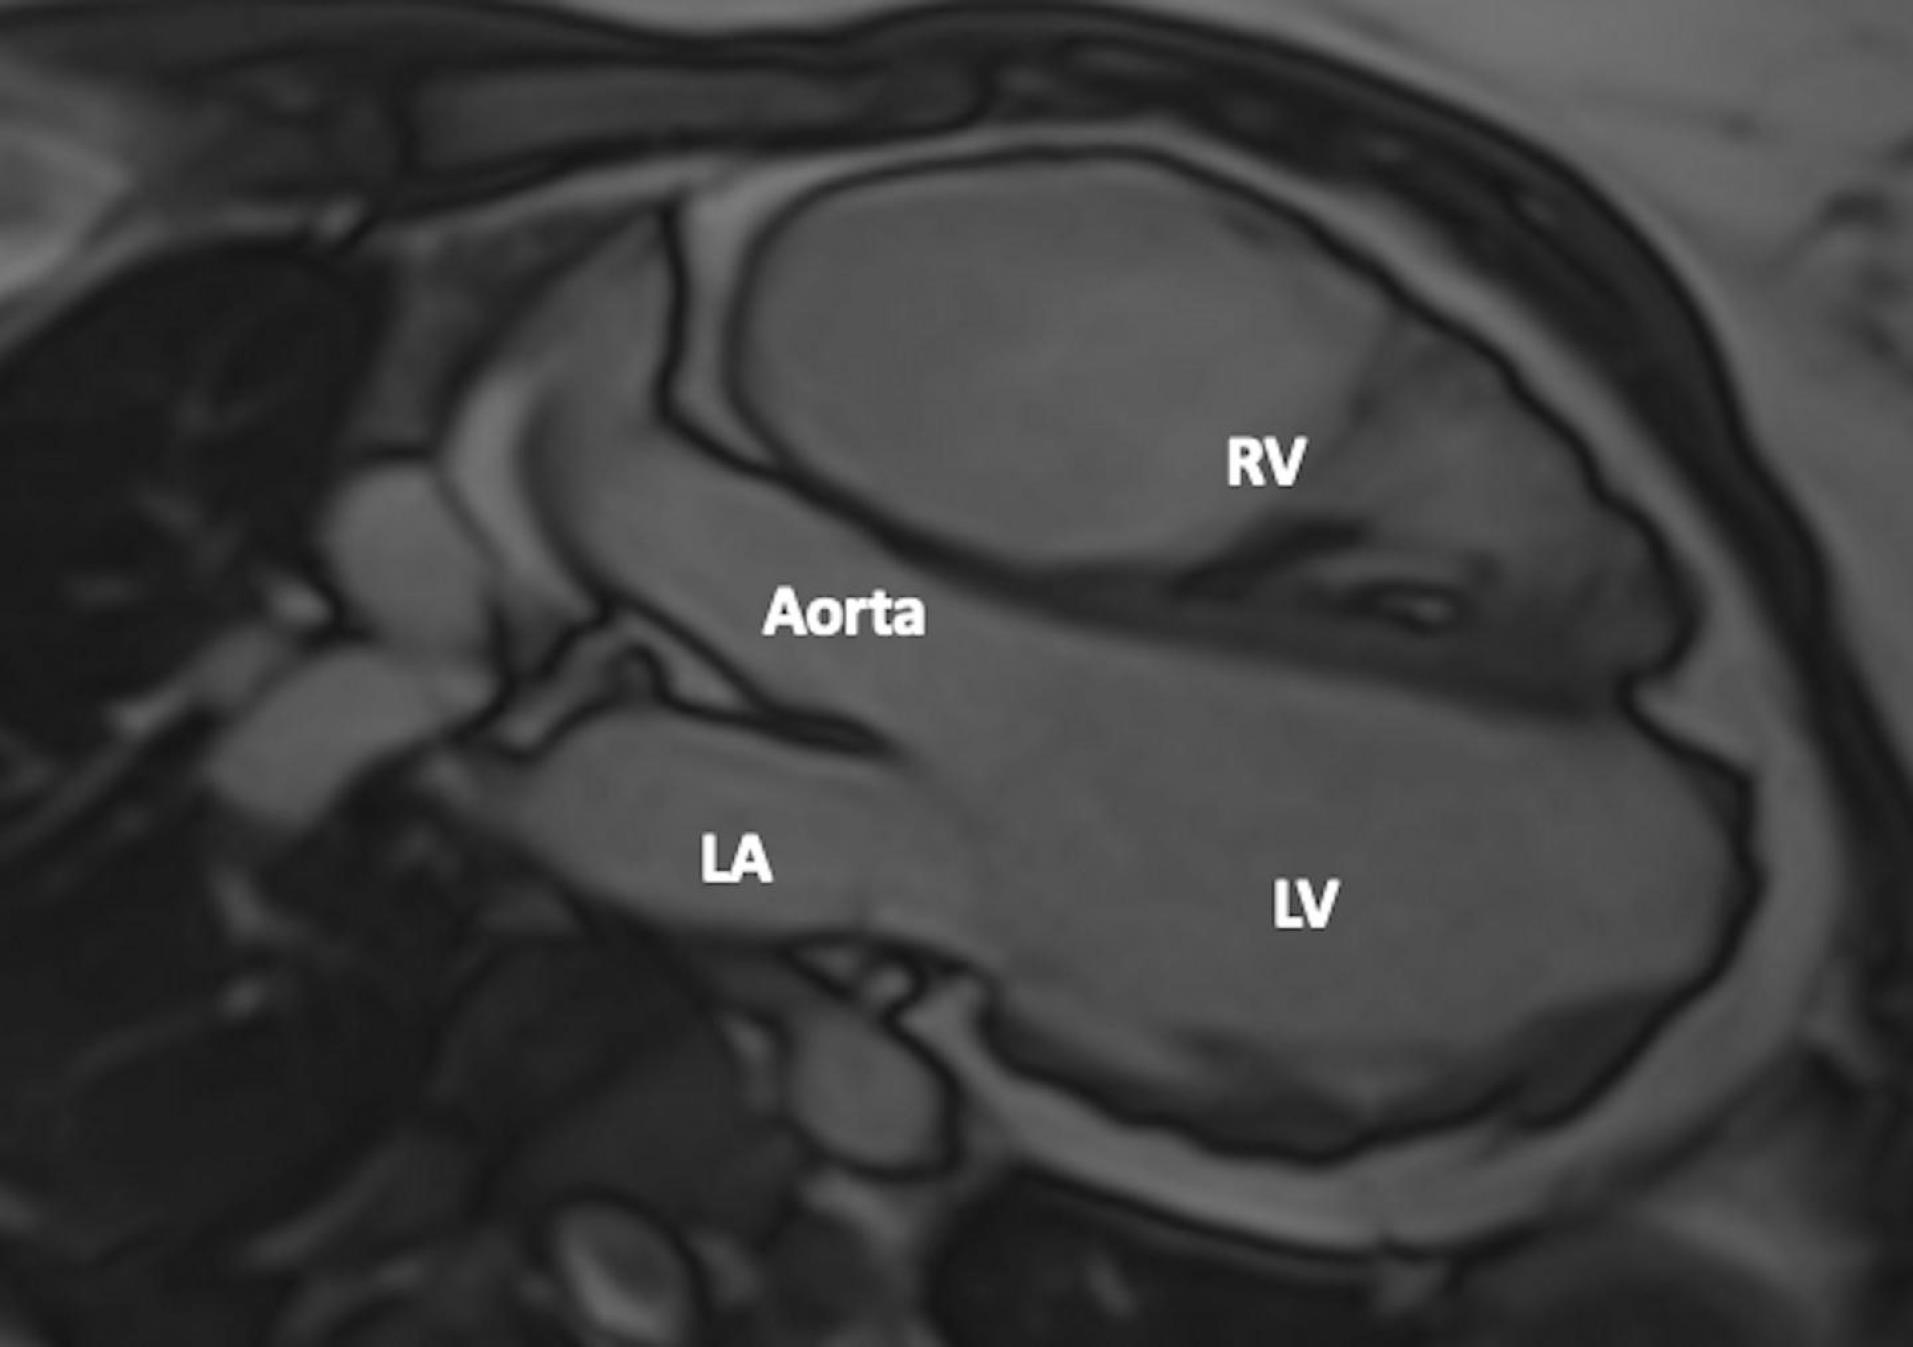

A 24-year-old female patient was admitted to our tertiary center with chest pain. She had no family history of cardiac disease or sudden cardiac death. Her electrocardiogram (ECG) was sinus rhythm and T wave negativity was detected in leads V1-5. (Figure 1) TTE showed a slight decrease in LV ejection fraction as 45%, prominently dilated right heart chambers, decreased RV functions (TAPSE: 11, tricuspid annular peak systolic velocity: 7.7), severe tricuspid regurgitation (Supplementary file 1, Video 1). Additionally, an image of 13.6 x 9.3 mm, hyperechoic, consistent with thrombus was observed in the lateral wall of the RV (Figure 2). No thromboembolism was reported in the pulmonary CTA. The patient underwent cardiac magnetic resonance imaging (CMR) for morphological and functional assessment of the heart. The CMR images showed enlarged RV and right atrium, severe hypokinesia of the RV, dyskinesia in the free wall of RV and paradoxical movement in interventricular septum, and wall irregularity in both ventricles (Figure 3). In the cardiac MRI, The LV ejection fraction was 49%, the LV end-systolic volume was 143 mL, end-diastolic volume was 73 mL, and stroke output was 60 mL. The LV end-diastolic volume index (LVEDVI) was 74 mL/m2, the LV end-systolic volume index (LVESVI) was 42 mL/m2. The RV ejection fraction was 20%, the RV end-systolic volume was 430 mL, end-diastolic volume was 343 mL, and stroke output was 87 mL. The RV end-diastolic volume index (RVEDVI) was 221 mL/m2, the RV end-systolic volume index (RVESVI) was 176 mL/m2. The late gadolinium images depicted diffuse enhancement in the right ventricular free wall and inferior wall. The left ventricular inferior septum showed midwall enhancement. A nodular mass was noted on the lateral wall of RV in the vicinity of the tricuspid valve which did not uptake gadolinium and was compatible with thrombus (Figure 4). As a result of these findings, genetic analysis was performed with a high suspicion of arrhythmogenic cardiomyopathy. The genetic analysis revealed a homozygous nonsense mutation in the desmoglein-2 gene, proven to be pathogenic in databases, and the diagnosis of arrhythmogenic cardiomyopathy was definitively confirmed with the findings from TTE, ECG, CMR, and genetic tests, which are part of the aforementioned Padua criteria.

Figure 3.

Wall Irregularity in Both Right and Left Ventricles. CMR 3-chamber view shows wall irregularity in both the right and left ventricles. FIGUR LEGEND: CMR: Cardiac Magnetic Resonance, LA: Left Atrium, RV: Right Ventricle, LV: Left Ventricle.